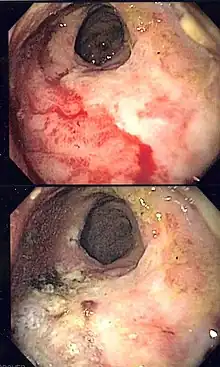

| Endoscopic image of radiation associated vascular ectasias (RAVE) before and after therapy with argon plasma coagulation. | |

Endoscopy is the mainstay of diagnosis for radiation damage to the rectum, with either colonoscopy or flexible sigmoidoscopy. RAVE is usually recognized by the macroscopic appearances on endoscopy characterized by vascular ectasias.[8] Mucosal biopsy may aid in ruling out alternate causes of proctitis, but is not routinely necessary and may increase the risk of fistulae development.[6] Telangiectasias are characteristic and prone to bleeding.[3] Additional endoscopic findings may include pallor (pale appearance), edema, and friability of the mucosa.

In contrast, RAVE and chronic radiation proctopathy usually is not self-limited and often requires additional therapies.[4] These include sucralfate, hyperbaric oxygen therapy, corticosteroids, metronidazole, argon plasma coagulation, radiofrequency ablation and formalin irrigation.[1][3][11] The average number of treatment sessions with argon plasma coagulation to achieve control of bleeding ranges from 1 to 2.7 sessions.[4]